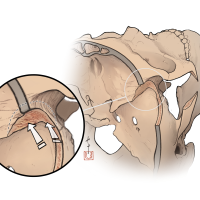

監修:谷川 緑野 / 札幌禎心会病院脳卒中センター

監修:太田 仲郎

監修:永田 雄一